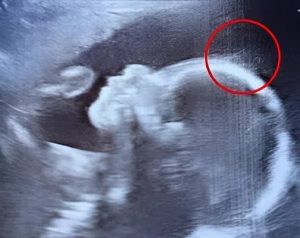

« Mais… est-ce que ce sont des cheveux que je vois ? », s’exclame-t-il, entre stupéfaction et amusement. Un collègue rejoint alors la salle et, observant l’écran, évoque avec humour la naissance prochaine d’une petite rock star. Sur l’image, de fins filaments semblent danser avec grâce dans le liquide amniotique, offrant un spectacle aussi rare que poétique.

Les professionnels de santé rassurent immédiatement Émilie : il est tout à fait courant que la pousse des cheveux débute in utero. Ce qui sort de l’ordinaire, ici, c’est leur densité et leur longueur, parfaitement discernables sur les images. Un tel niveau de détail est rarement capté lors d’un examen standard.

Quelques semaines plus tard, la petite Jade voit le jour… et confirme pleinement l’étonnante prédiction de l’échographie. Elle arbore une **chevelure remarquablement dense et longue**. Le personnel de la maternité est subjugué : la crinière du bébé évoque davantage celle d’un enfant de plusieurs mois que d’un nouveau-né à peine sorti du ventre de sa mère.

Les pédiatres confirment que si certains nourrissons naissent avec des cheveux, l’ampleur de ceux de Jade reste tout à fait exceptionnelle. L’échographie s’est révélée être une annonciatrice parfaitement exacte de cette caractéristique unique.